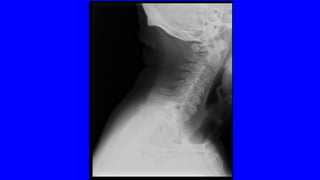

• ENCUESTA DE SALUD DEL INE: LA PREVALENCIA DEL DOLOR LUMBAR Y/O

CERVICAL EN ESPAÑA ES DEL 25% (> 10 MILLONES)

• PRIMER MOTIVODE CONSULTA MÉDICA • < 45 AÑOS ES EL PRIMER PROBLEMA INCAPACITANTE • EN EEUU ES EL MAYOR GASTO EN SALUD (IT, ANALÍTICAS, RX,RNM) • IMPLICA SUFRIMIENTO, DIFICULTAD PARA EL DESCANSO, TRISTEZA Y AL FINAL DEPRESIÓN: COMPONENTE PSICOSOCIAL • ENCUESTA DE SALUD DEL INE: LA PREVALENCIA DEL DOLOR LUMBAR Y/O CERVICAL EN ESPAÑA ES DEL 25% (> 10 MILLONES)